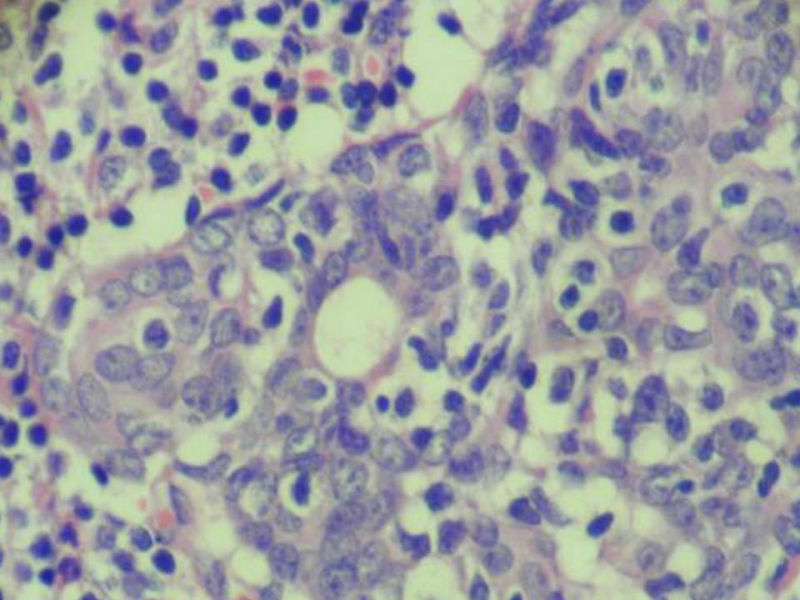

腮腺肿物:良性淋巴上皮病变(Mikulicz病)

女,71岁,腮腺肿物,临床诊断混合瘤。